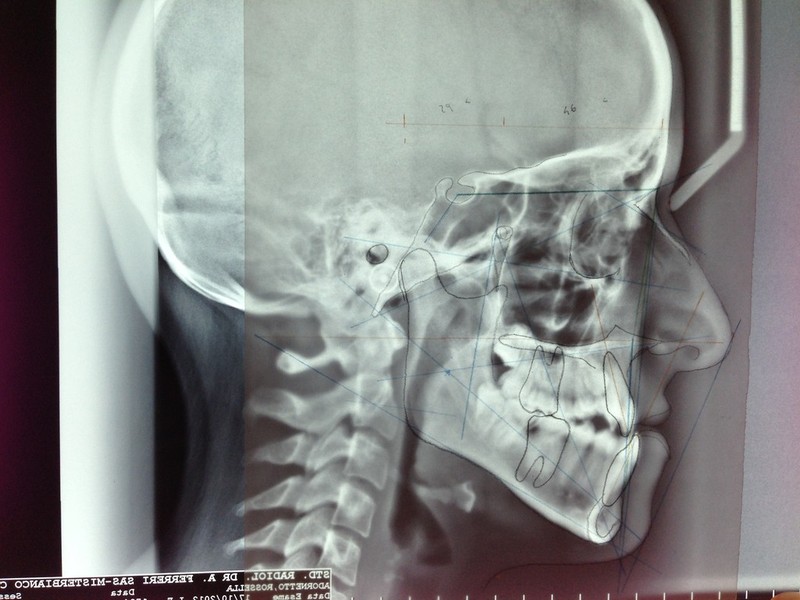

Paziente candidato a intervento di chirurgia Ortognatica